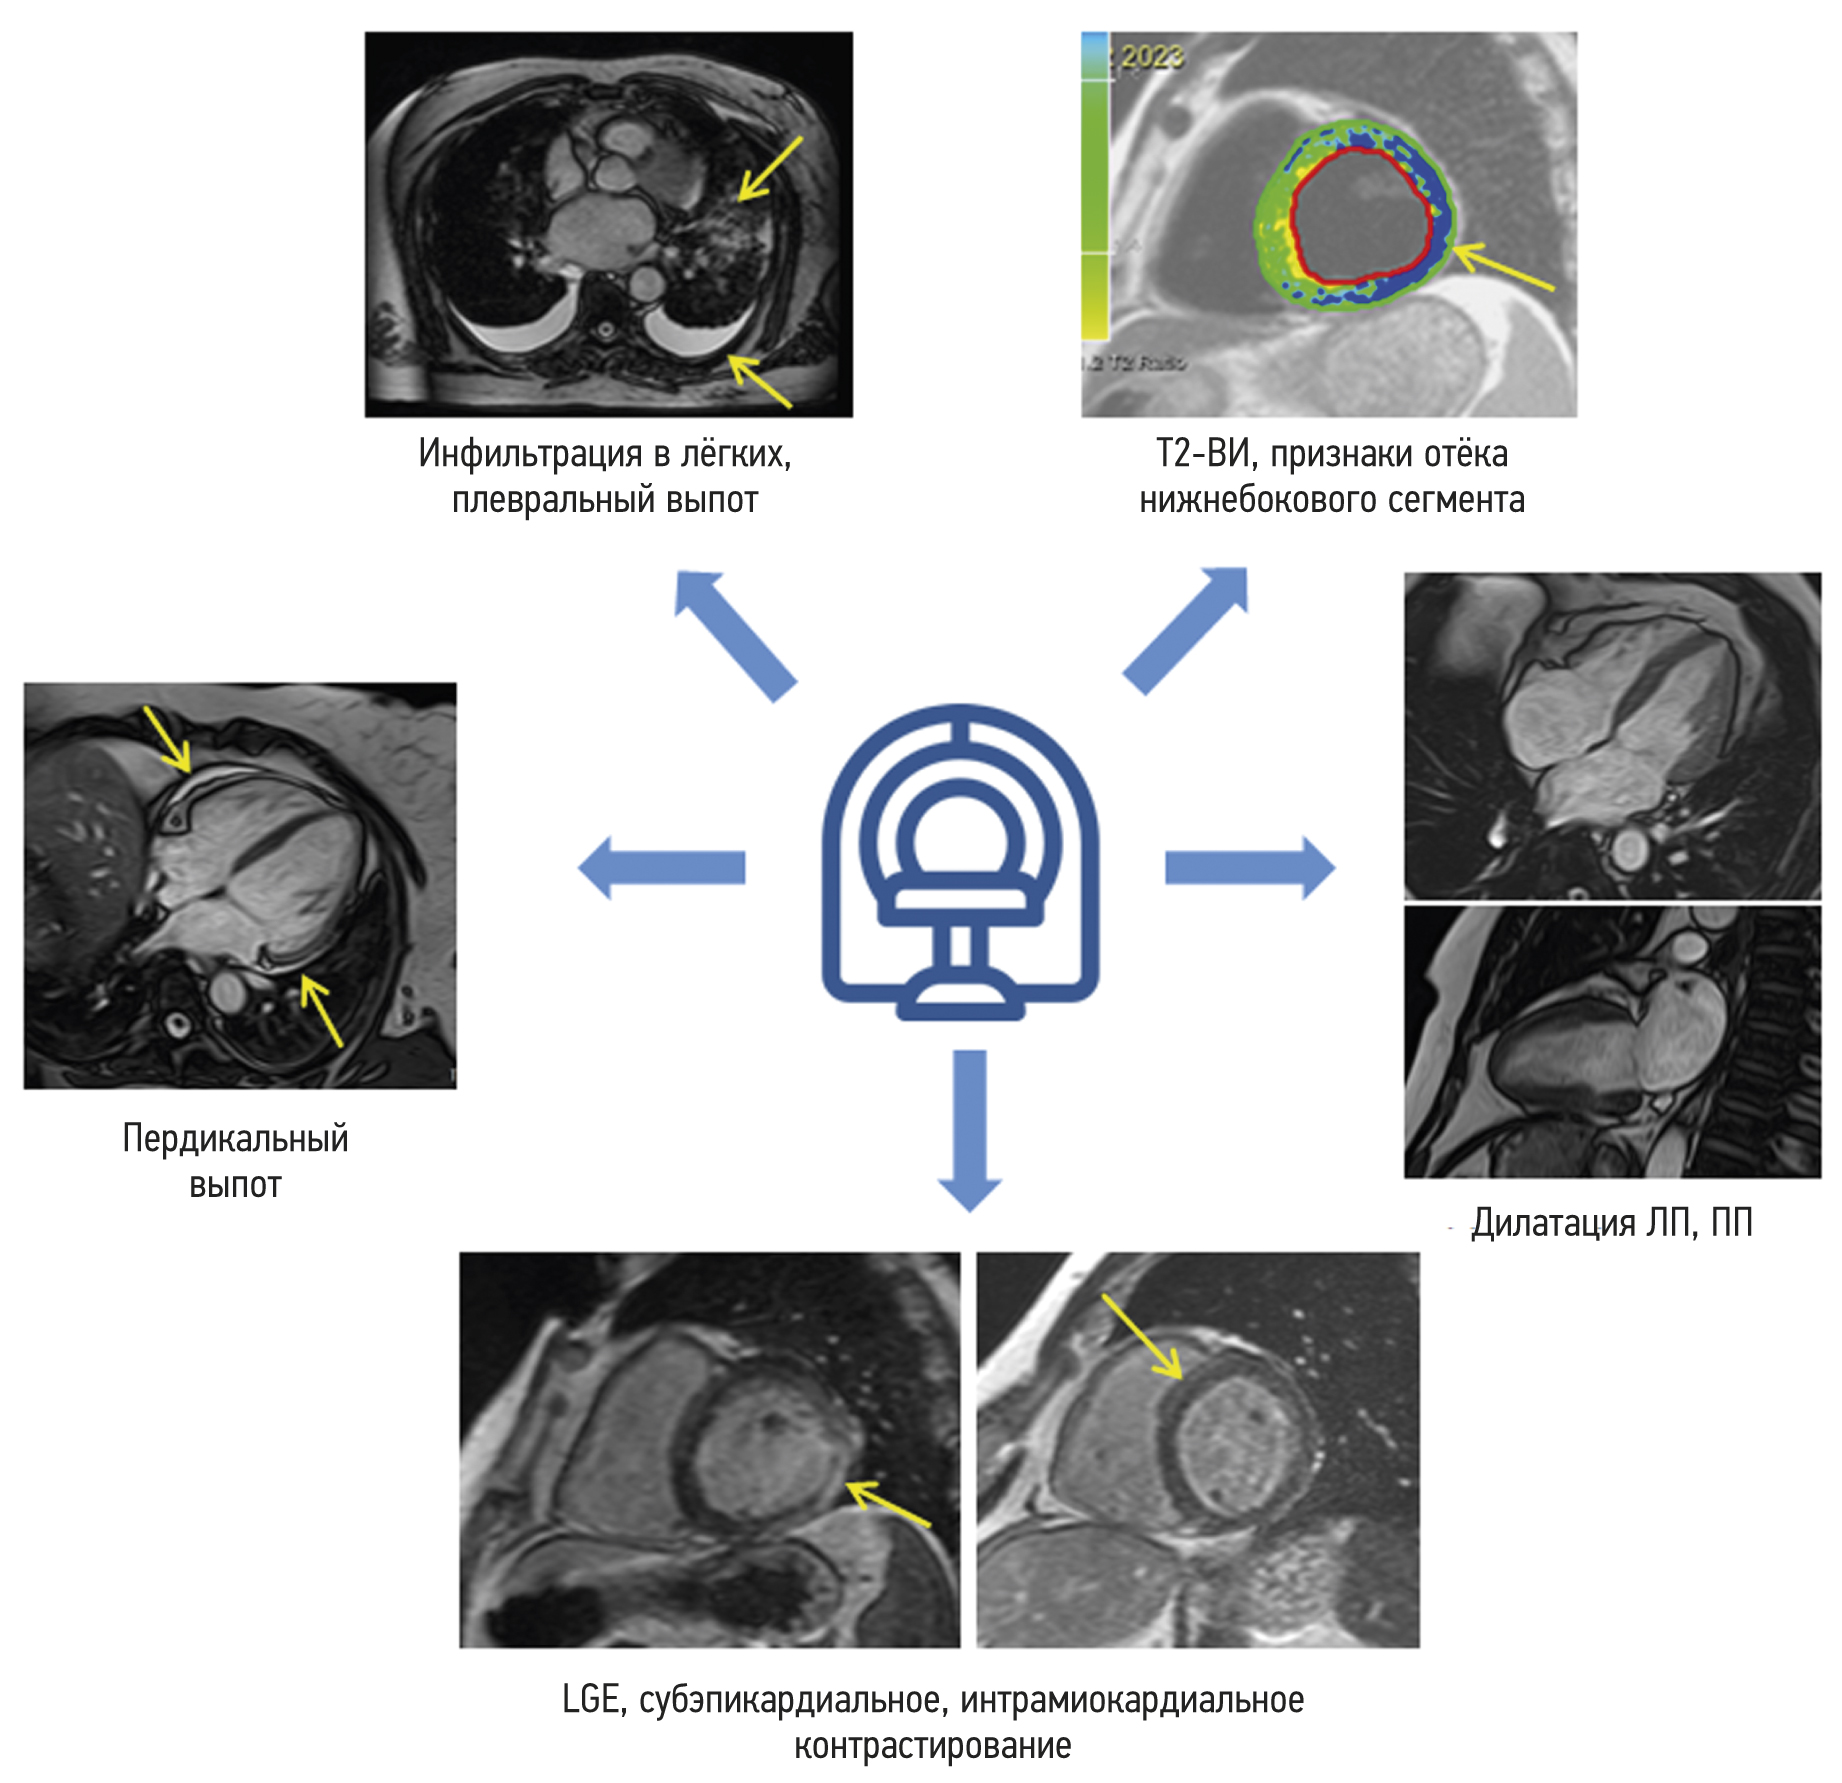

Магнитно-резонансная томография сердца у пациентов, переболевших коронавирусной инфекцией (COVID-19)

Обоснование. Нередким осложнением коронавирусной инфекции (COVID-19) является миокардит.

Цель ― сравнить различные паттерны повреждения миокарда у пациентов, перенёсших COVID-19, и пациентов допандемийного периода по данным магнитно-резонансной томографии сердца с парамагнитным контрастным усилением.

Материалы и методы. В ретроспективное исследование включено 47 пациентов, которым выполняли магнитно-резонансную томографию сердца с парамагнитным контрастным усилением для исключения острого миокардита. В группу 1 вошли 34 пациента с перенесённой коронавирусной инфекцией, подтверждённой результатами исследования мазка со слизистой носо- и/или ротоглотки методом полимеразной цепной реакции, в группу 2 ― 13 человек, магнитно-резонансную томографию сердца которым проводили до начала пандемии коронавирусной инфекции (2017 г).

Результаты. Средняя продолжительность от появления жалоб до проведения магнитно-резонансной томографии составила 166 дней. Снижение толерантности к физическим нагрузкам обнаружено у 77% пациентов, боль в области сердца, одышка и сердцебиение ― у 14 (42%), 30 (88%) и 28 (85%) пациентов группы 1 соответственно. В группе 2 отмечены одышка у 4 (30%) пациентов, боли в области сердца ― у 9 (69%), сердцебиение и/или ощущение ритма сердца ― у 6 (46%). У пациентов группы 1 поражение миокарда носило более распространённый характер, из них у 1/3 сохранялись усиление лёгочного рисунка и выпот в плевральную полость. В группе 1 мужчины имели более низкую фракцию выброса левого желудочка, меньшие показатели глобальной продольной деформации и более высокие функциональные показатели левого предсердия (p <0,05). У женщин статистические различия отмечались только по количеству поражённых сегментов миокарда левого желудочка.

Заключение. Вирус SARS-CoV-2 вызывает распространённое поражение сердца с вовлечением значительного количества сегментов миокарда. Среди мужчин достоверно чаще развиваются поствоспалительные осложнения в виде нарушения сократительной функции левого желудочка и левого предсердия. Полученные результаты указывают на необходимость дальнейшей оценки долгосрочных последствий перенесённого COVID-19 на сердечно-сосудистую систему. Магнитно-резонансная томография сердца с контрастированием в данном случае может быть чувствительным инструментом визуализации для выявления тяжести поражения сердца.